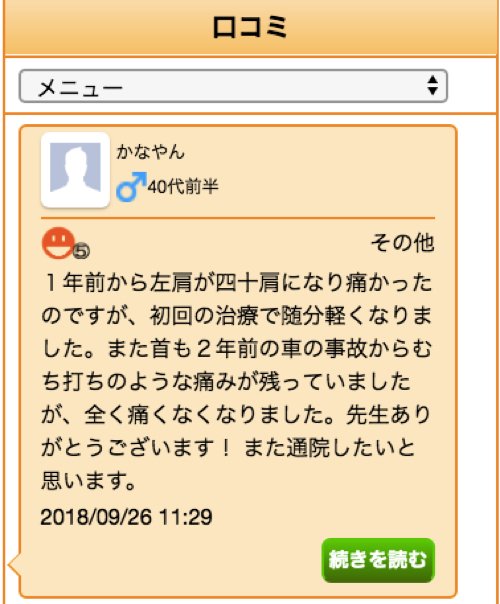

ご丁寧にクチコミまでしてくださいました!

ありがとうございます。

1年前から左肩が四十肩になり痛かったのですが

初回の治療で随分軽くなりました。

また首も2年前の車の事故からむち打ちのような痛みが

残っていましたが、全く痛くなくなりました。

先生ありがとうございます! また通院したいと思います。

こちらこそ、ありがとうございます^^